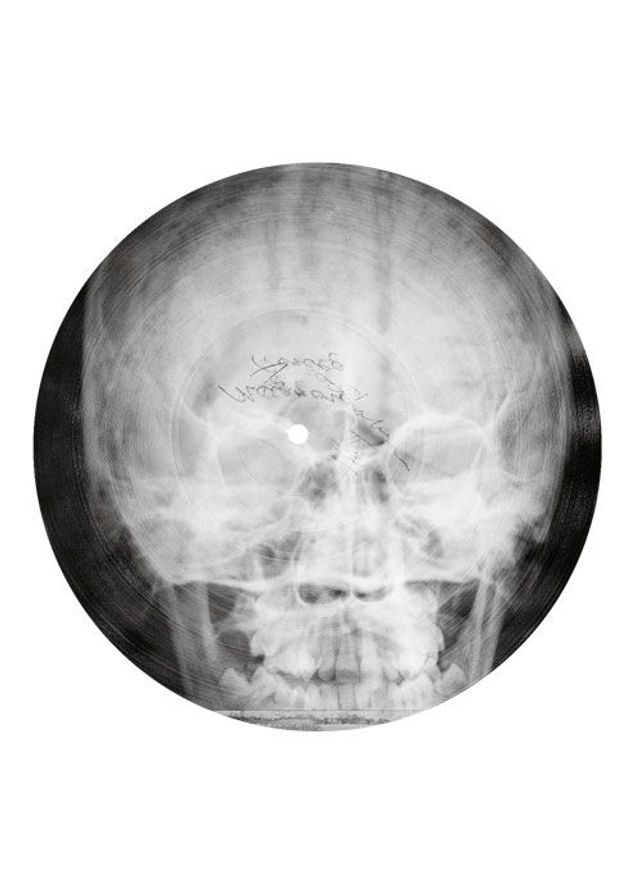

»Was haben wir für einen schönen Abend«, singt Anna Kapitány, während sich die Röntgenaufnahme eines menschlichen Schädels auf dem Grammophon dreht. Musik auf Skeletten – das wäre eine wunderbare Marketing-Idee für eine Black-Metal-Band. Aber zu Kapitánys heiterem Bigband-Swing tanzten die Ungarn in den Dreißiger- und Vierzigerjahren. Diese Lieder wurden live gespielt und im Radio übertragen. Nur für die Ewigkeit ließ sich ihre Musik schwer festhalten: Im Krieg war Schellack selten, das Harz aus den Ausscheidungen der Lackschildlaus musste aus Indien importiert werden. Also suchten Musikliebhaber und Mitarbeiter des ungarischen Radios eine Alternative – und fanden sie in Krankenhäusern.

Die Zelluloidfolien, auf denen gebrochene Rippen, ausgerenkte Gelenke, tuberkulöse Lungen abgebildet wurden, waren gerade dick und haltbar genug, dass man mit einer Plattenschneidemaschine Tanzmusik oder Ansprachen von Politikern hineingravieren konnte. Die biegsamen Platten wurden mal mehr, mal weniger sorgfältig in eine runde Form geschnitten, sodass sie auf den Teller des Grammophons passten. Für die Nadel war es egal, ob sie von Rillen im Schellack oder im Zelluloid zum Schwingen gebracht wurde. Zu lange durfte das Stück nicht dauern – auf eine Scheibe mit 23 bis 25 Zentimetern Durchmesser passten nicht viel mehr als drei Minuten. Ein halbes Jahrhundert zuvor waren die Röntgenstrahlen entdeckt und das Grammophon erfunden worden, nun verschmolzen sie zu einer Technik.

Nach dem Fall des Eisernen Vorhangs hat der ungarische Fotograf József Hajdú die Schönheit dieser Scheiben neu entdeckt und besonders gelungene Exemplare aus unterschiedlichen Sammlungen fotografiert. Bei vielen ist heute nicht mehr nachvollziehbar, welche Musik oder welcher Sprecher da zu hören ist. Hajdú ist davon begeistert, dass die Scheiben in zweifacher Hinsicht Themen unserer Zeit vorwegnahmen: »Zum einen sind sie Recycling, zum anderen eine frühe Form von Multimedia.« Die anonymen Raubkopierer, sagt Hajdú, hätten sich sichtlich Mühe gegeben, besonders eindrucksvolle Röntgenaufnahmen für ihre Aufnahmen zu wählen.

Fotos: József Hajdú